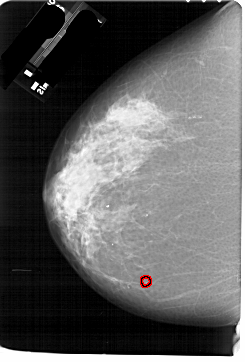

A_1774_1.LEFT_MLO

LEFT_MLO LINES 6841 PIXELS_PER_LINE 4321 BITS_PER_PIXEL 12 RESOLUTION 43.5 OVERLAY

FILE: A_1774_1.LEFT_MLO.OVERLAY

TOTAL_ABNORMALITIES 1

ABNORMALITY 1

LESION_TYPE CALCIFICATION TYPE PLEOMORPHIC DISTRIBUTION CLUSTERED

ASSESSMENT 4

SUBTLETY 1

PATHOLOGY BENIGN

TOTAL_OUTLINES 1

BOUNDARY